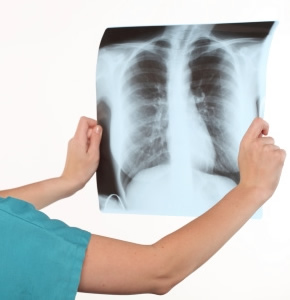

Nos hemos olvidado de la Tuberculosis sin embargo está aquí para recordarnos su presencia y su vigencias, confrontarnos con la resistencia a los tratamiento y su diseminación a pesar de que dábamos por hecho que la teníamos bajo control.

La tuberculosis ataca principalmente los pulmones, sin embargo puede estar prácticamente en cualquier lugar del cuerpo humano (ganglios, riñones, intestino, hueso, cerebro etc..), se dice que son contagiadas 10 personas promedio por año si alguien no recibe el tratamiento adecuado, además de que quién sufre la enfermedad sin tratamiento puede morir a los 5 años (50% de los diagnosticados).

El germen ingresa a los pulmones con las secreciones contaminantes, en el 95% el organismo por si solo lo puede controlar y 5% con una no muy buena respuesta inmune puede contagiarse. Otros exámenes que se recomiendan son la baciloscopía con tinsión de BARR que puede dar el resultado en 24-48 horas, cultivo de ZN que se reporta hasta en 60 días.